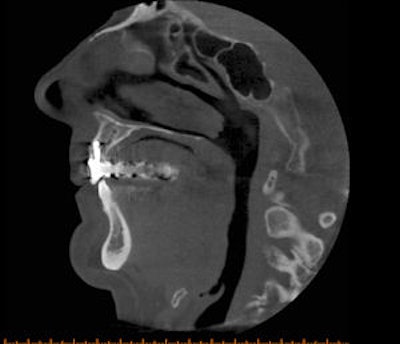

![]() |

| Cone-beam CT images from two different patients. The top CT image was taken to evaluate the mandible for implant purposes; the other was taken to evaluate the maxilla for implant purposes. The images show how much more of the head was exposed than needed to be. Also, one CT was done at 0.25 voxels, which is more resolution than is needed for a typical implant CT. Images courtesy of Dr. Bernard Friedland. |